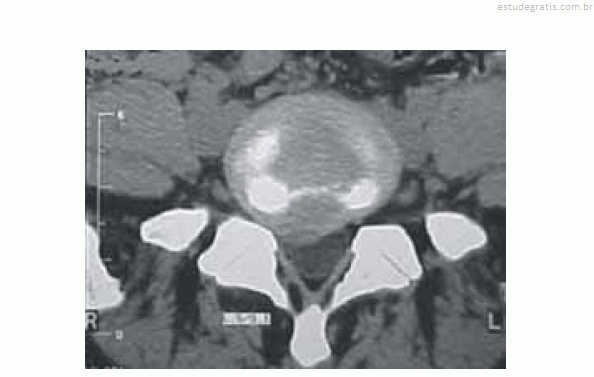

Um empregado de uma fábrica de móveis com 47 anos de idade queixa-se, há algum tempo, de lombalgia, mas continua trabalhando normalmente. Certo dia, teve queda de cima de um caminhão e não conseguiu mais andar devido à dor na região lombar e no membro inferior à direita; ficou em repouso por uma semana, mas continuou com os sintomas álgicos. Voltou ao serviço médico quando realizou novo exame físico, sendo constatadas algumas alterações. O médico solicitou uma tomografia computadorizada (TC) da coluna lombar, cuja imagem é reproduzida abaixo, e o encaminhou ao neurologista.

A TC de coluna lombar evidencia lesão compatível com hérnia discal como causa dos sintomas referidos pelo paciente. Tal patologia é mais comum nos segmentos torácicos e lombares.A TC de coluna lombar evidencia lesão compatível com hérnia discal como causa dos sintomas referidos pelo paciente. Tal patologia é mais comum nos segmentos torácicos e lombares.